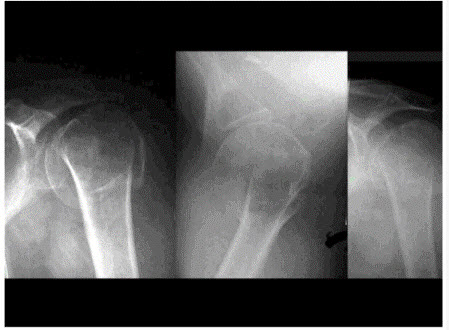

15、单项选择题

男,28岁,摔伤后肩部剧痛,活动受限,请结合影像学检查,选出最可能的诊断()

A.柯莱斯骨折

B.肱骨头骨折

C.肱骨外科颈骨折

D.加莱阿齐骨折

E.蒙泰贾骨折

点击查看答案

本题答案:微信扫下方二维码即可打包下载完整带答案解析版《★北京住院医师外科Ⅰ阶段》或《北京住院医师外科Ⅰ阶段:骨科》题库